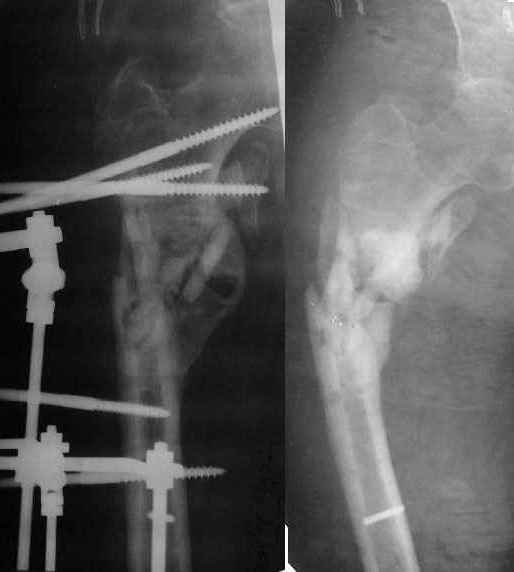

[Ortho] Ложный сустав в/3 плечевой кости!

Неудачный остеосинтез пластиной: поломка винтов. После удаления

сформирался гиполастический ложный сустав. Остеосинтез АВФ,

циклическая компрессия-дистракция в области ложного сустава привела к

формированию хорошей рентгенологической костной мозоли. Через 1,5

месяца ходил в аппарате без дополнительных средств опоры. Через 6

месяцев после клинической пробы - демотаж. Через 4 месяца после

демонтажа - лизис костной мозоли, рецидив деформации.